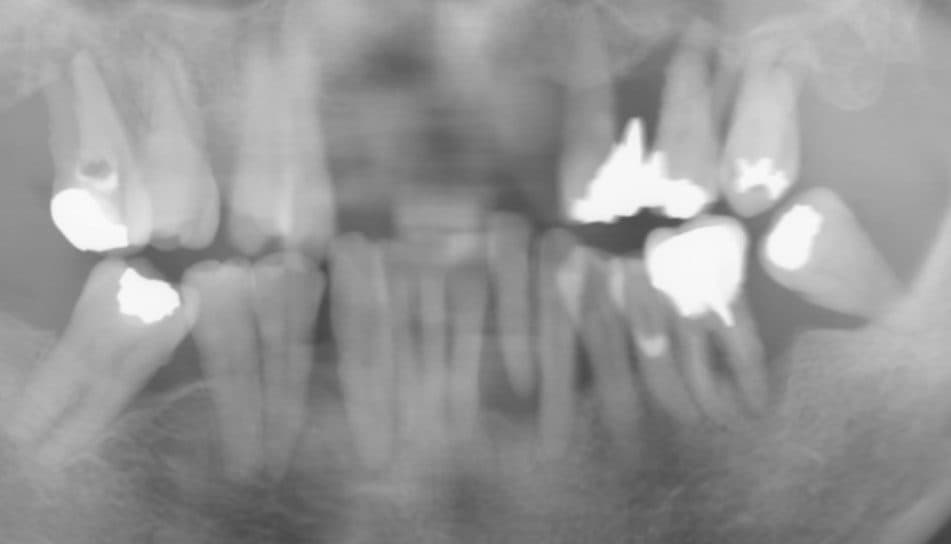

下図 2017年のレントゲン写真

8年前に比べると、かなり歯を支える骨が吸収してしまっているのがわかります。

下の前歯に関しては、骨が一切無く歯肉にくっついている状態でした。

ご本人曰く、痛みは今まで全くなかったそうです。